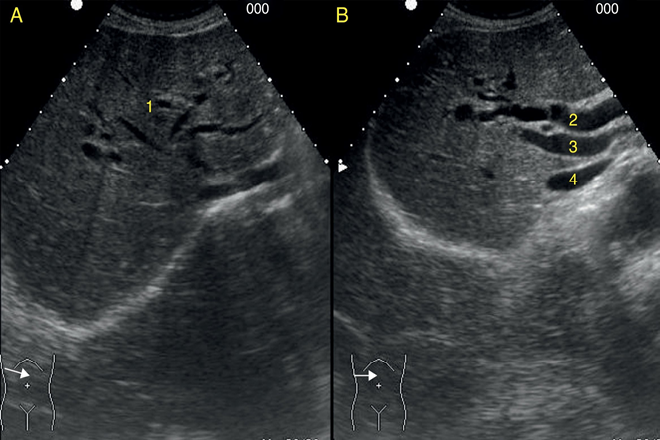

El engrosamiento de la pared de la Vesícula biliar (VB) se observa con frecuencia en pacientes con hepatitis A aguda. En pacientes con hepatitis viral aguda, el engrosamiento de la pared vesicular  puede ser secundario al proceso inflamatorio en el hígado adyacente. Por otra parte  la severidad de la necrosis del hígado parece influir en el grado de engrosamiento de la pared.

En el caso de la hepatitis viral, la pared VB engrosamiento es el patrón más frecuentemente observado en los Estados Unidos. Además, la frecuencia de engrosamiento de la pared VB es mayor en pacientes con una infección viral que en pacientes con otras causas potenciales de engrosamiento de la pared VB. Tres hipótesis se han propuesto para explicar el mecanismo de engrosamiento de la pared GB en pacientes con hepatitis aguda: